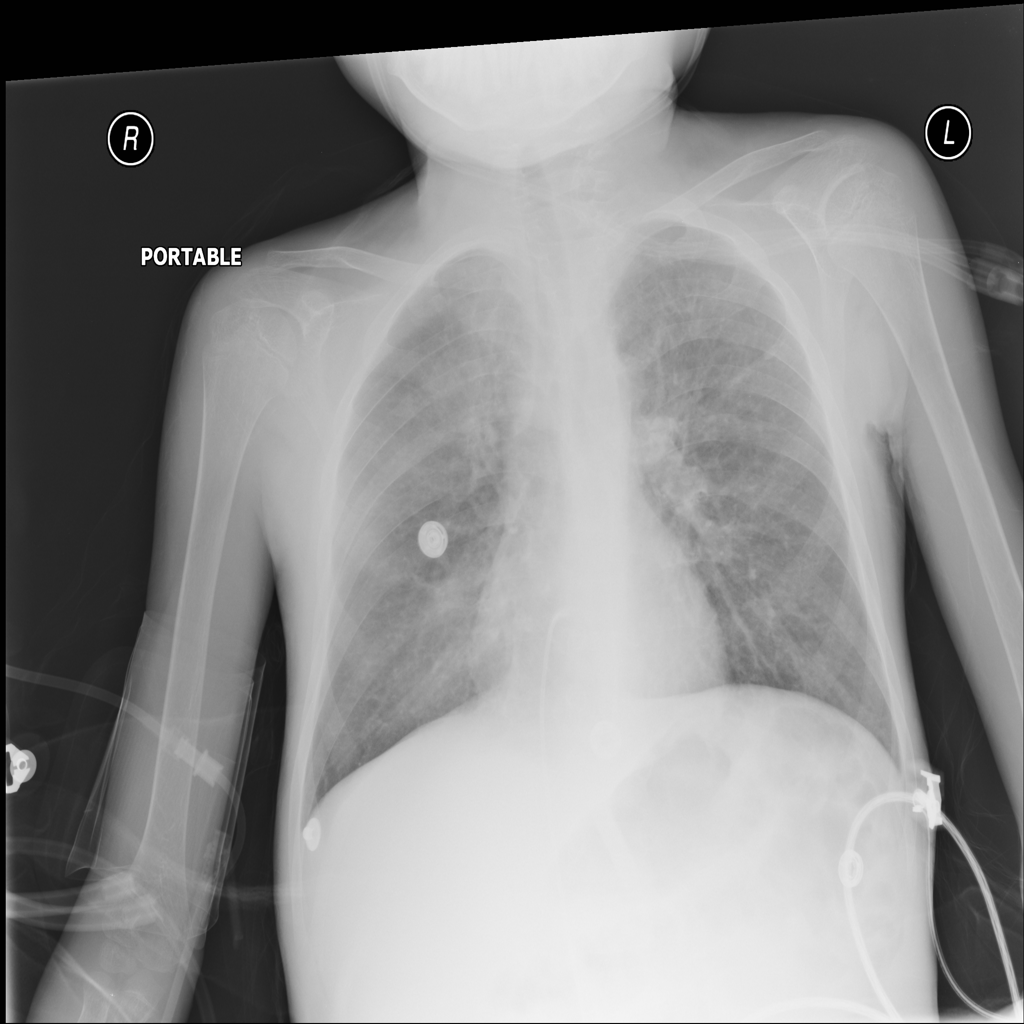

PAT-C1A7 · IMG-055Consolidation

PAT-C1A7 · IMG-055

AP